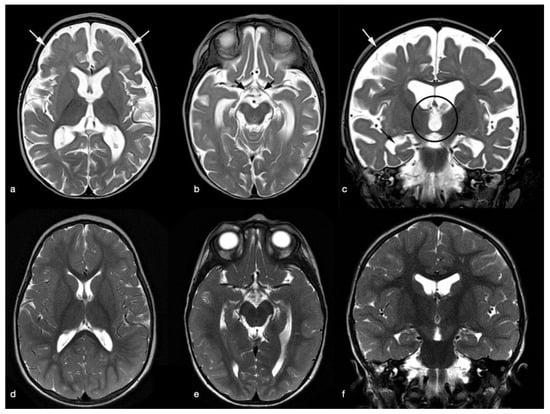

Clinical and Brain Imaging Findings in a Child with Vitamin B12 Deficiency

2. Case Presentation